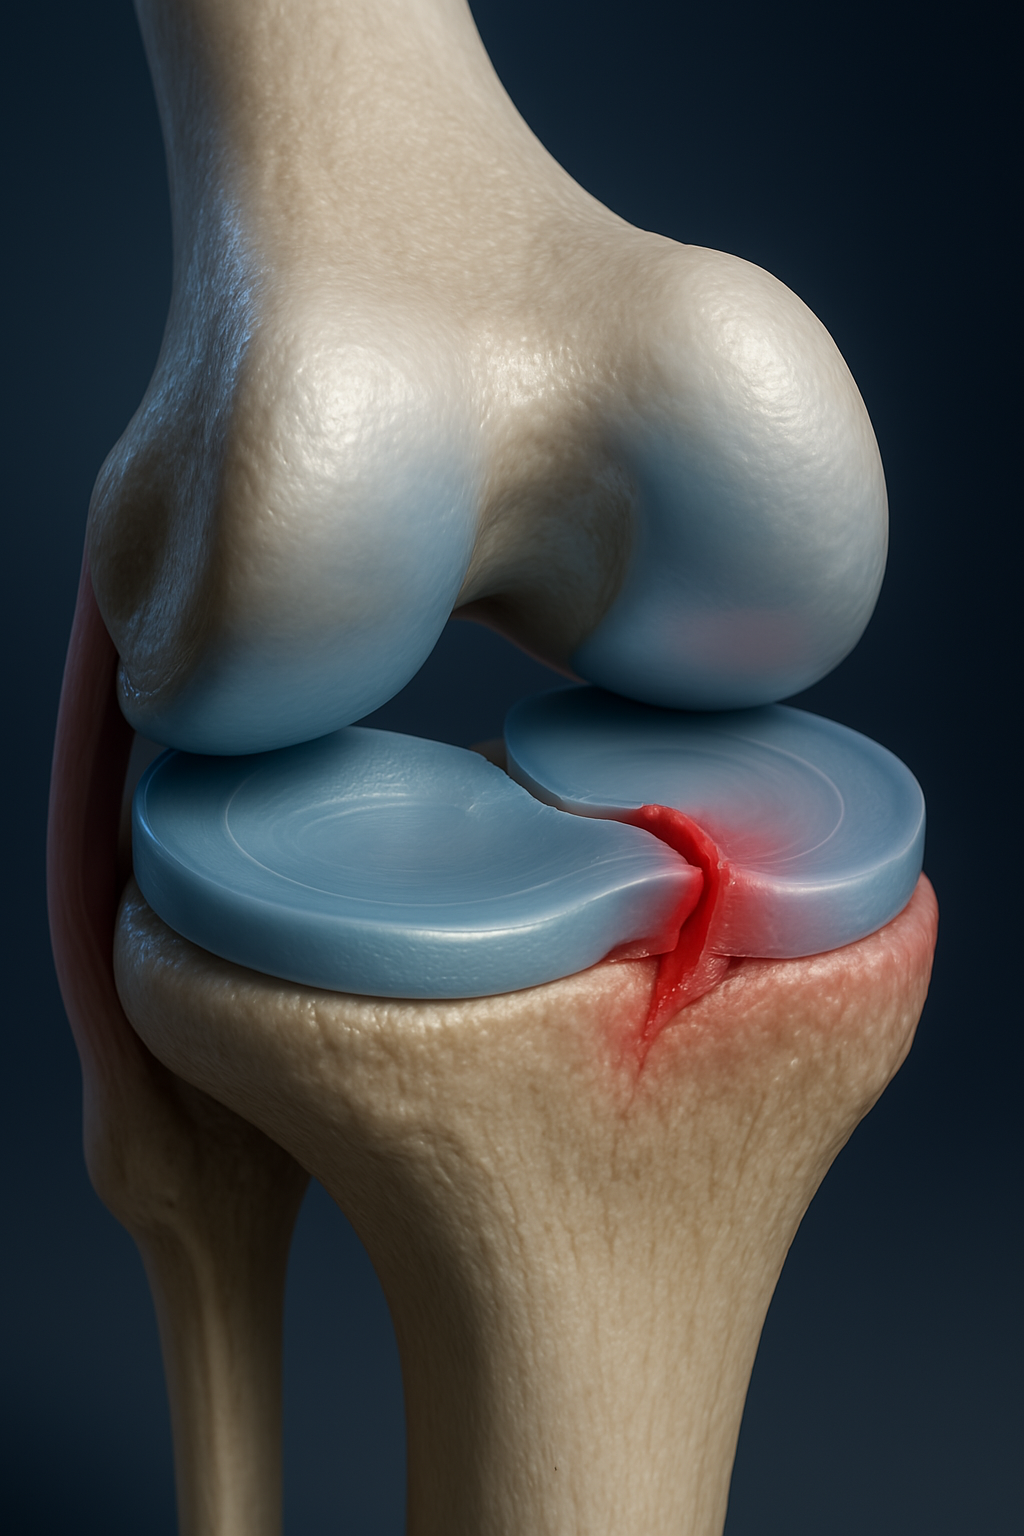

Ortopedia e Traumatologia | Cirurgia do Joelho